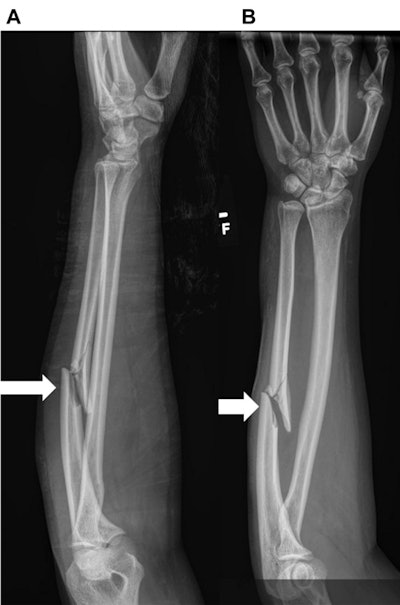

A 42-year-old woman with a history of “hit by boyfriend.” (A) Frontal and (B) lateral radiographs of the left forearm show a nondisplaced fracture of the mid-diaphysis of the ulna (wide bold arrows). There is an old healed fracture of the distal radius with hardware. Images courtesy of the Journal of the American College of Radiology.Further analysis of the cases of domestic violence indicates that nondisplaced fractures of the ulna were telltale signs of abuse: 95% of women who were victims had nondisplaced isolated ulnar fractures, compared with 43% of women who were not victims.